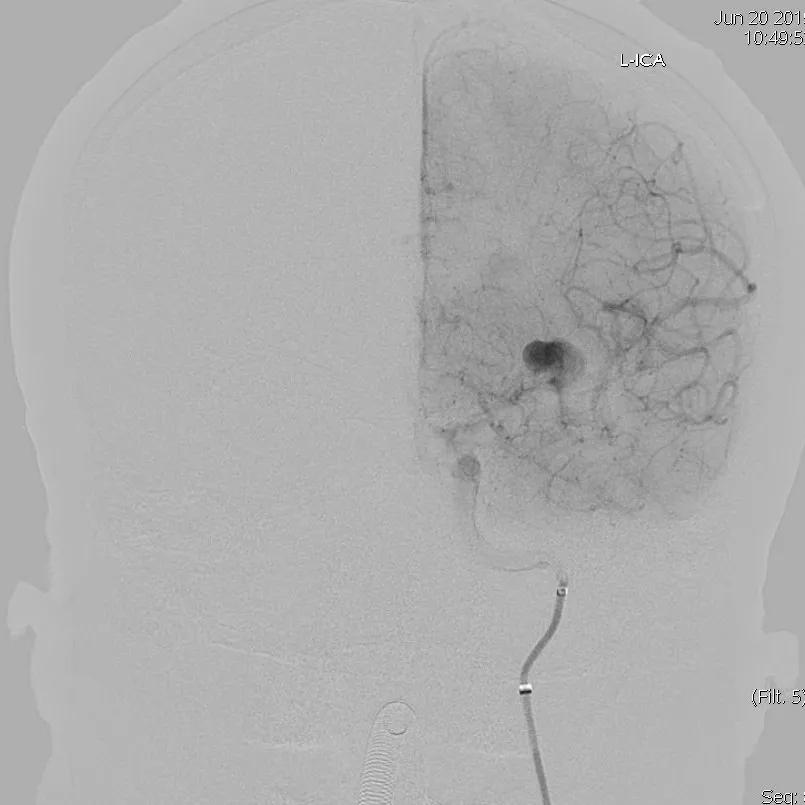

患者于入院前1天无明显诱因突发头。外院头颅CTA示:颅内动脉瘤。我院行DSA示:左侧大脑中动脉动脉瘤。

全脑血管造影可见左侧大脑中动脉动脉瘤,瘤体最大径:16.7mm,瘤颈宽:8.3mm。

Synchro 14微导丝导引支架导管,远端送入左侧中动脉下干远端困难,支架导管内穿行Tracxseed微导丝,双导丝导引支架导管顺利进入左侧中动脉下干远端,尾部链接Y阀1个,压力带1个。

经支架导管,置入Tubridge® 3.0×30mm,释放位置良好。

复查造影,动脉瘤造影剂明显滞留,各血管及分支通畅,流速正常。手术结束。